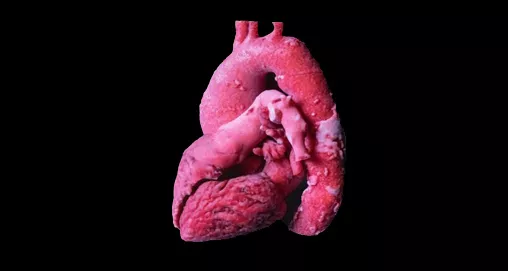

Создание 3D-моделей костей, мускулов, легких и сердечно-сосудистой системы из снимков МРТ и КТ Создание 3D-моделей костей, мускулов, легких и сердечно-сосудистой системы из снимков МРТ и КТ

Разрабатывайте уникальные индивидуальные 3D‑модели, соответствующие всем стандартам качества, с помощью набора медицинских инструментов Mimics Innovation Suite для анатомического проектирования на основе 3D‑изображений.

Модули для решения задачи:  Mimics Base / X-Ray / CT Bone / Muscle Segmentation / Pulmonology / C&V Segmentation

Преимущества:  Изготовление ортопедических и кранио-фасциальных имплантатов с индивидуальным дизайном для сложной хирургии, комплексной терапии онкологии или для устранения дефектов / Моделирование хирургических шаблонов, позволяющих точно определить будущее расположение имплантата и успешно провести операцию / Создание анатомических моделей для более оперативной коммуникации между хирургами и быстрого принятия клинических решений / Предоперационное планирование для транскатетерной замены аортального клапана